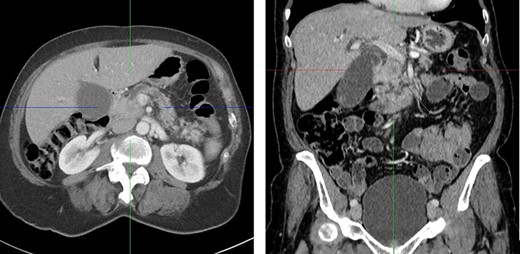

A computed tomography (CT) scan was performed and showed a poorly defined, hypodense mass in the pancreatic head measuring 2.5 cm and causing obstruction of the common bile duct and pancreatic duct. These findings were consistent with a pancreatic head carcinoma (Fig. 1).

CT scan with a poorly defined 2.5 cm hypodense mass in the pancreatic head causing obstruction of the common bile duct and pancreatic duct. Axial and coronal plane.